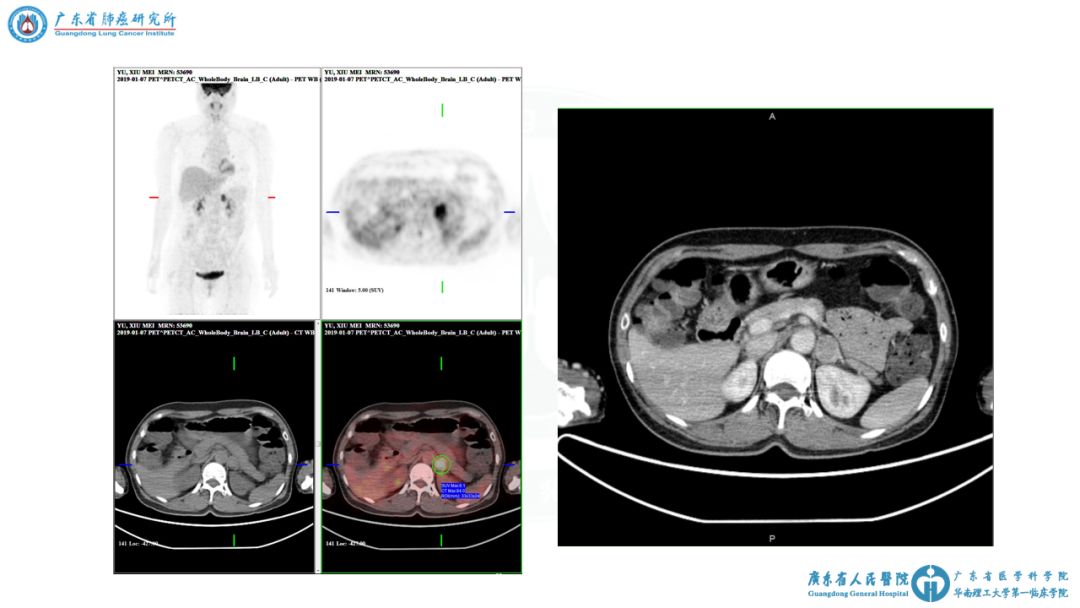

图表资料

讨论要点2:多结节的寡转移?

② 患者肾上腺病灶是否为寡转移癌?

① 双侧多原发肺癌伴左侧肾上腺转移,cT1b(m)N0M1b,IVa期。